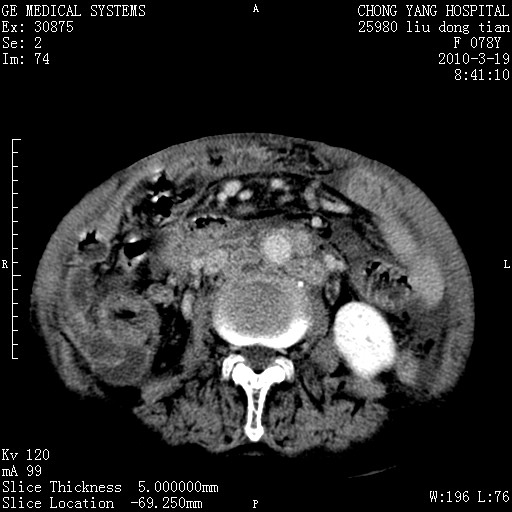

标题: CT25199:F 78Y 腹胀半年 消瘦乏力 [打印本页]

胆囊壁增厚并明显强化,胆囊癌伴多发转移瘤可能性大,淋巴瘤不除外,右肾囊肿,胸腹水.

考虑nhl,肝、脾、腹膜腔及腹膜后多发淋巴结受侵,腹水,右肾囊肿,慢性胆囊炎,右侧少量胸腔积液。

胰头有肿块形成,胰头ca伴肝脾、腹膜腹膜后转移

胆囊有软组织影有强化,支持胆囊癌,肝脾、腹膜后淋巴结转移。

nhl的淋巴结多围绕主动脉,而且主动脉会移位,所以不考虑nhl。

分开来讲:肝左叶、尾叶病灶有不均强化像肝癌;

脾脏病灶无强化,像多发囊肿或淋巴管瘤,不除外淋巴瘤(低强化);

胆囊增生性病变:胆囊癌,腺肌增生症,慢性胆囊炎;

肝门、胰腺头、腹膜后多个团块: 淋巴瘤,转移;

腔静脉肝内段细小有无布加可能?

一元论最好了 淋巴瘤所致改变; 胆囊癌转移不像,胆囊周围肝组织清晰,肝癌淋巴结转移?三元论都不止。

最后报的胰头癌多发转移,脾脏单独考虑囊肿或淋巴管瘤。